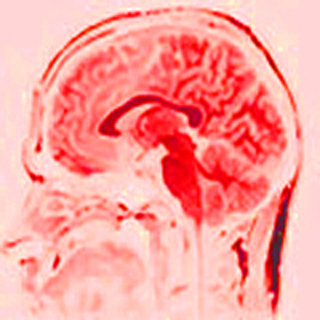

Magnetic resonance image of adult human brain. (Image courtesy of MIT Department of Brain and Cognitive Sciences.)